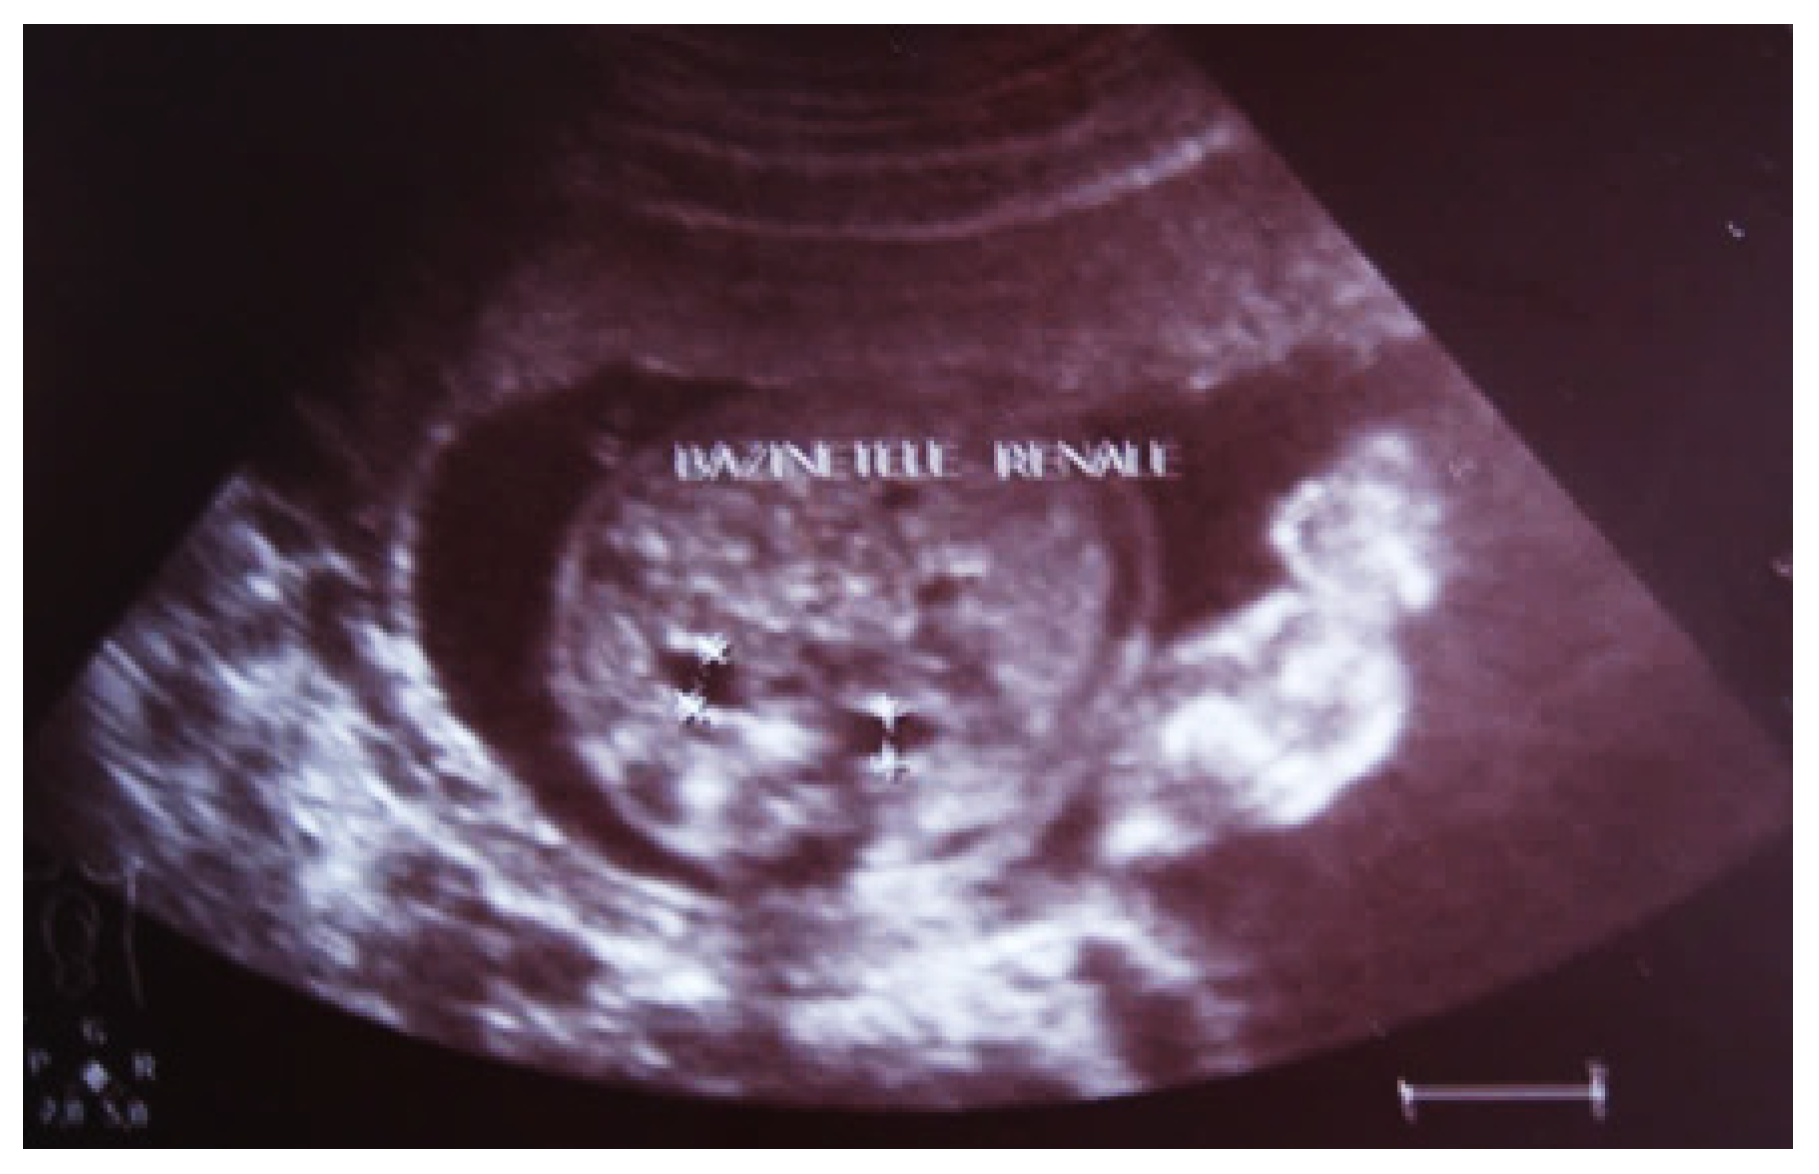

Our experience with congenital malformations of the urinary system refers to the following clinical case (Figure 2, Figure 3, Figure 4, Figure 5, Figure 6, Figure 7, Figure 8 and Figure 9). In the first case, during pregnancy, the 21-week ultrasound determined bilateral renal pyelectasia. The fetus had hydronephrosis on the right; at 31 weeks, it had bilateral hydrocalconephrosis; and at 32 weeks, bilateral pyelectasia. It suffered premature birth at 36 weeks, with complicated anomalies of the forces of contraction, prolonged birth, and birth weight of 2200 g. Postnatal ultrasonography was supplemented by intravenous urography, and bilateral hydronephrosis was determined. Hydrocalconephrosis on the left was discovered. The complete diagnosis was established: congenital renal malformation; bilateral pyelectasia; bilateral hydronephrosis; hydrocalconephrosis on the left; and severe reduced glomerular filtration rate (GFR), GFR > 2SD below mean.

Figure 9. Ultrasound of the urinary system in a 12-day-old newborn. Hydrocalconephrosis on the left (a) and ureteral hydronephrosis on the right (b).